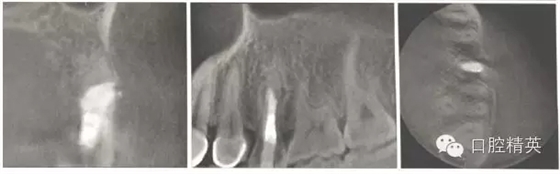

10個(gè)月后復(fù)查,頰側(cè)黏膜色澤正常(圖5),患者咀嚼正常,無不適。X線片示:根管斷端見MTA致密影像,根中側(cè)暗影減?。▓D6)。錐形束CT示斷端處MTA連接良好,斷端兩側(cè)已有骨質(zhì)形成(圖7)。

圖6l0個(gè)月后復(fù)診時(shí)X線片。

圖7l0個(gè)月后復(fù)診時(shí)初診錐形束CT影像